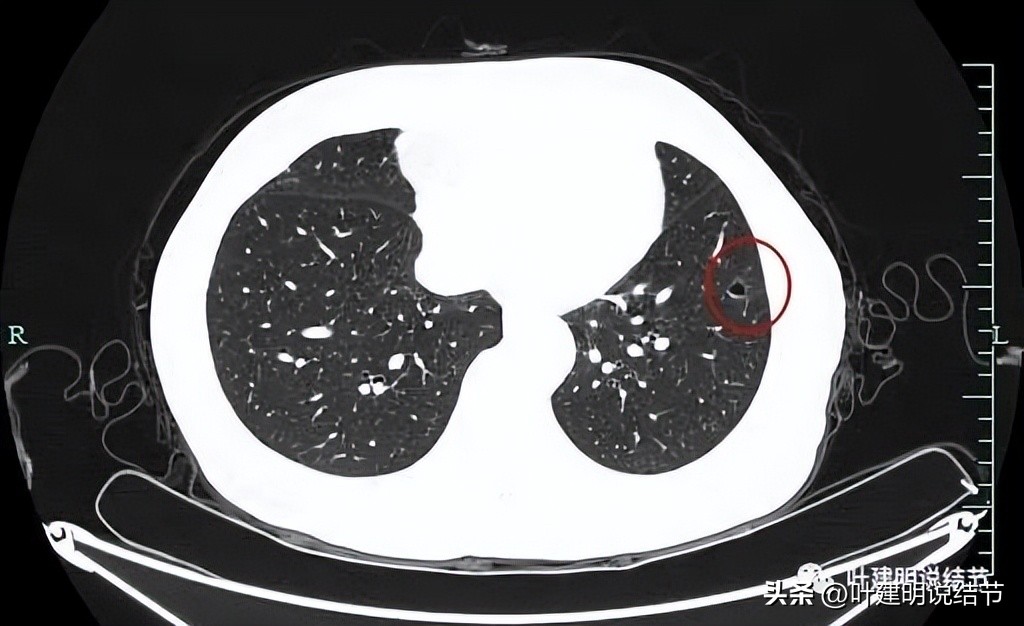

左下叶有磨玻璃结节,有明显高密度成分成线条状与环形,磨玻璃密度部分轮廓较清,不太规则。

病灶中间有空腔,空腔较圆,部分囊壁密度略高。

我当时的回复是认为纯磨伴空腔,原位癌可能性大,也可能是不典型增生,仍可再随访。大概当时认为密度过高部分像纤维增生或慢性炎,而磨玻璃部分的本身还没有实性成分,囊壁也基本上是磨玻璃密度的。

病灶轮廓清,中间有实性成分,磨玻璃部分瘤肺边界清,表面也不平,考虑肿瘤可能性大。

病灶仍是囊腔型,壁不均,表面不平,部分囊壁密度略高。

再看左下叶的主病灶,此层见其是磨玻璃密度,轮廓较清,内部密度欠均匀。

有明显血管征,血管进入后有分支发出,病灶表面显得有毛刺样。

病灶中间有空腔。

囊壁较薄,但不均匀,有的地方还是显略厚了点的。

靶重建后发现病灶囊腔型,桔色箭头示进入的血管有异常增粗,而且壁显得毛糙;黄色箭头示空腔;红色箭头示整体轮廓较清;绿色箭头示有磨玻璃成分,虽然密度较低;蓝色箭头示病灶略有胸膜牵拉影响,只是力较弱而已。